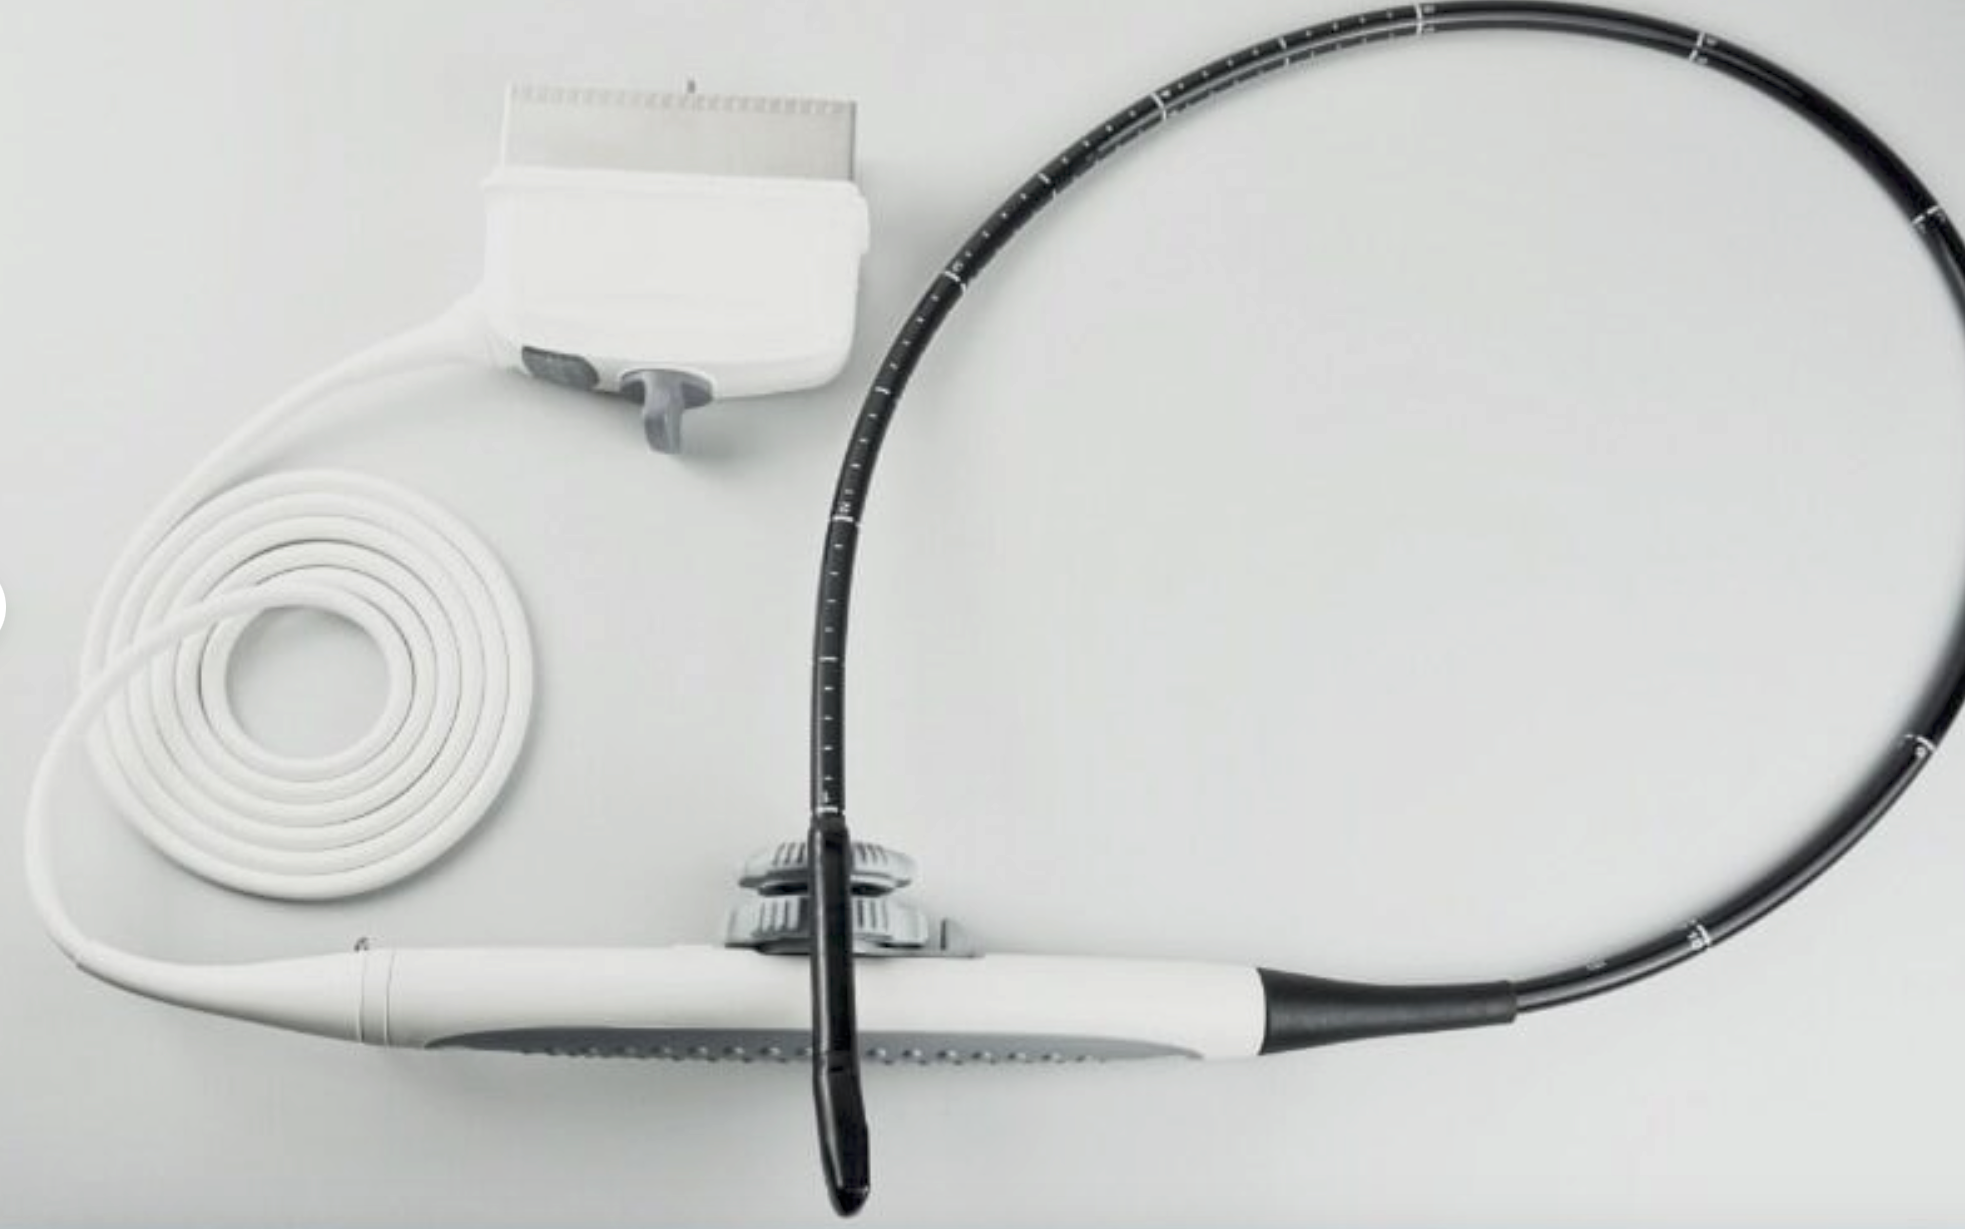

2014 GE L8-18i -RS probe for GE Ultrasound

Sale price$ 7,170.06